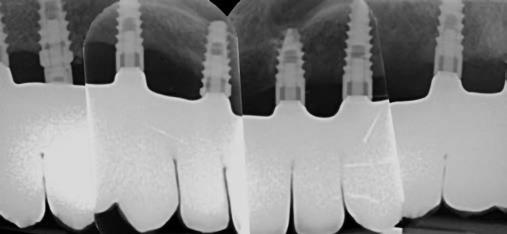

A gyógyulási időszakot követően a csontos gyógyulás ellenőrzése és az implantáció tervezése céljából állcsonti CT-felvételt készítettünk. A CT-felvételen tökéletes csontos gyógyulást észleltünk, az alveoláris csont volumene

Fergeteges

teljes mértékben megtartott, a vertikális augmentáció a tervezettnek megfelelő eredményű volt (13–15. ábra), a klinikai kép is ennek megfelelően alakult, optimális menynyiségű keratinizált ínnyel és azt adekvát sebészi technika eredményeképpen megtartott vesztibulummal (16–17. ábra). Az alsó és felső állcsontba 4-4 darab Bredent COPA Sky implantátumot ültettük, D1-D2 csontminőség mellett,

35 Ncm primer stabilitást mértünk. Nyílt gyógyulási protokollt alkalmazva az ínyformázókat is behelyeztük, amelyek körül az ínyt csomós öltésekkel zártuk (18–20. ábra) Amennyiben lehetséges, mindig nyílt gyógyulási protokollt választunk, így biztosítva elegendő időt a lágyrészek maturációjához (29). Kiemelendő, hogy az irodalmi adatoknak (30, 31, 32) és saját tapasztalatunknak megfelelően az íny biotípusának jelentős, pozitív irányú változását észleltük. Az implantátumokra 180 nap gyógyulási időszakot követően (minden implantátum stabilitása Periotesttel –8-as értékű volt) hagyományos lenyomatvételi módszer és egyéni értékű artikulátor használatával a fogtechnikus (D1 Dental Kft., Garamvári Csaba) overdenture típusú fogpótlást készített (21. ábra)

A protetikai rehabilitációt követően 9 hónappal az alveoláris struktúrák stabilak, a röntgenfelvételen a csontállomány megtartott, a beteg panaszmentes, rágó funkciója kifogástalan, az esztétikai eredménnyel teljes mértékben elégedett (22–23. ábra)